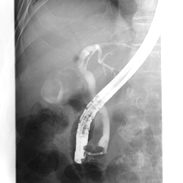

血管造影検査

血管内に細い管(カテーテル)やワイヤーを入れて検査を行い、バルーンやステントを使って治療を行います。当院では4台の装置が稼働しており、それぞれの装置の特長を生かして冠動脈や不整脈、大動脈や末梢血管、頭部血管などの治療を行っています。またハイブリッド手術室では、カテーテル治療と外科的治療を併せた手術を行っています。

さらに定期的に患者被ばくを管理し、適したカテーテル検査および治療を受けて頂けるように尽力しています。